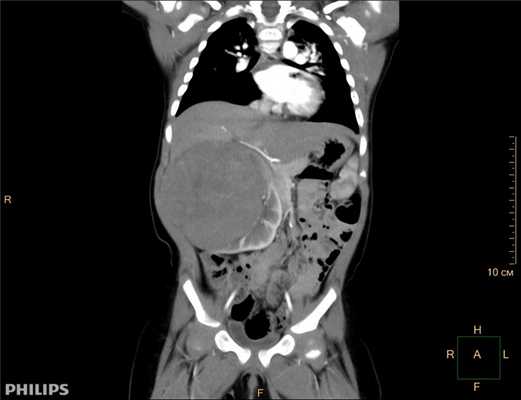

- Компьютерная томография органов брюшной полости и забрюшинного пространства с оральным и внутривенным контрастированием (см. рис. 1).

Рисунок 1. КТ брюшной полости ребенка с большой нефробластомой с метастазами в печень.

Клинически: при пальпации опухоль в проекции правой почки до 12 см в диаметре. Общеклинические исследования в пределах возрастной нормы. При КТ органов брюшной и грудной полости: КТ-картина объемного образования правой почки без признаков интрапульмональных метастазов (см. рис. 2). УЗИ брюшной полости: в проекции правой почки солидно-кистозное образование 101ґ114ґ99 мм, объемом 500 мл, васкуляризация активная, интактная часть почки 57ґ12ґ40 мм. Объемное образование правой почки — опухоль Вильмса. Предварительный диагноз: опухоль Вильмса правой почки, 2-я стадия.

Ребенку проведена предоперационная химиотерапия. На 5-й неделе лечения КТ-контроль показал уменьшение опухоли в размерах до 90ґ80ґ100 мм (см. рис. 3).